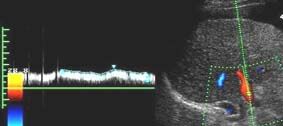

8.Оценка печеночной гемодинамики включает исследование основных сосудов печени - печеночных вен, воротной вены и печеночной артерии, а также их крупных ветвей. Предпочтительно использовать режим ЦДК, позволяющий уточнить не только наличие, но и направление кровотока. Помимо сосудов печени в режиме ультразвуковой ангиографии исследуются круглая связка печени и передняя брюшная стенка - вдоль белой линии живота с использованием линейного датчика, что позволяет более точно выявить наличие кровотока в параумбиликальной вене. ЦДК является высокоинформативным методом в определении обратного (гепатофугального) кровотока в воротной вене и наличия кровотока в порто-кавальных коллатералях. Используя ЦДК, можно быстро определить - является ли визуализируемая трубчатая структура сосудом, оценить наличие и направление кровотока в нем. При ЦДК во внутрипеченочной части воротной вены и в ее ветвях отмечается красный сигнал спектра, соответствующий обычному (гепатопетальному) направлению кровотока при стандартных настройках аппарата. В печеночных венах в норме регистрируется синий сигнал спектра, соответствующий кровотоку от печени, к нижней полой вене и правым отделам сердца.

Визуализация печеночных вен не представляет существенной трудности как из интеркостального, так и из субкостального доступов. При исследовании печеночных вен по методике, предложенной Bolondi (1991), контрольный объем, составлявший 1/3 просвета сосуда, помещается в среднюю печеночную вену на расстоянии 3-6 см от места впадения ее в нижнюю полую вену, что позволяет исключить влияние последней на форму допплеровского спектра. В норме спектр кровотока в печеночных венах трехфазный и зависит от фаз сердечного цикла (см. рис).